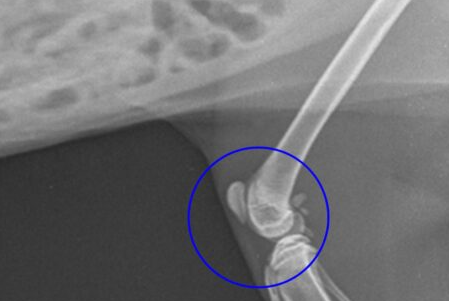

- 또한, 슬개골이 지속적으로 이탈하면서 대퇴골의 활차구(슬개골이 움직이는 홈)가 얕아지거나 변형되고, 경골(정강이뼈)의 뒤틀림 등 뼈의 구조적인 변형까지 동반될 수 있습니다.